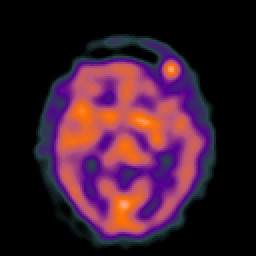

Hypertensive Encephalopathy, overlay -- Slice #12

[Home][Help][Clinical] Slice 12